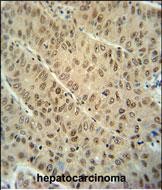

分类: 科研抗体货号: P30820别名: DDB1- and CUL4-associated factor 10, WD repeat-containing protein 32, DCAF10, WDR32应用: WB,IHC,FCM反应种属: Human